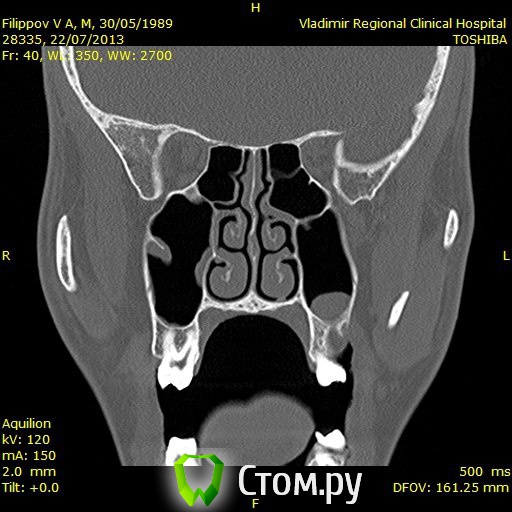

Доброго времени суток,помогите пожалуйстабеспокоит заложенность носа уже 3ий год,обший ослабленный иммунитет что выражается в частых простудах,возраст 25 лет,причина этого гдето в зубах,так как кроме этого проблем небыло никогда,когда начились эти проблему начал ходить к стомалогам мне сделали порядка 7 пломб,в одном был пульпит,как пульпит переличили стало легче но не до конца ,затем на мскт увидели кисту под депульпированной 7кой,

вот зуб пролечил у ильи мера,в 2 этапа,первый раз он сделал,и залили лекарство и сказал зуб врядли сохраним,через месяц второй прием все доделал и сказал что все хорошо,после этого общее состояние стало хуже,возможно из-за того что врач сказал что все с пульпы сливалось прямо в пазуху, вот это делали в марте ,после этого сделал мскт киста с зуба увеличилась с 1см до 1,5см, я лег в больничку местную и мнее ее вырезали,после этого прошел 1 месяц улучшений нет все также заложенность в носе и пониженный иммунитет,не подскажите что делать?кисту просто вырезали резекцую корня зуба не делали вот снимки до вырезания кисты после первого раза лечения каналов